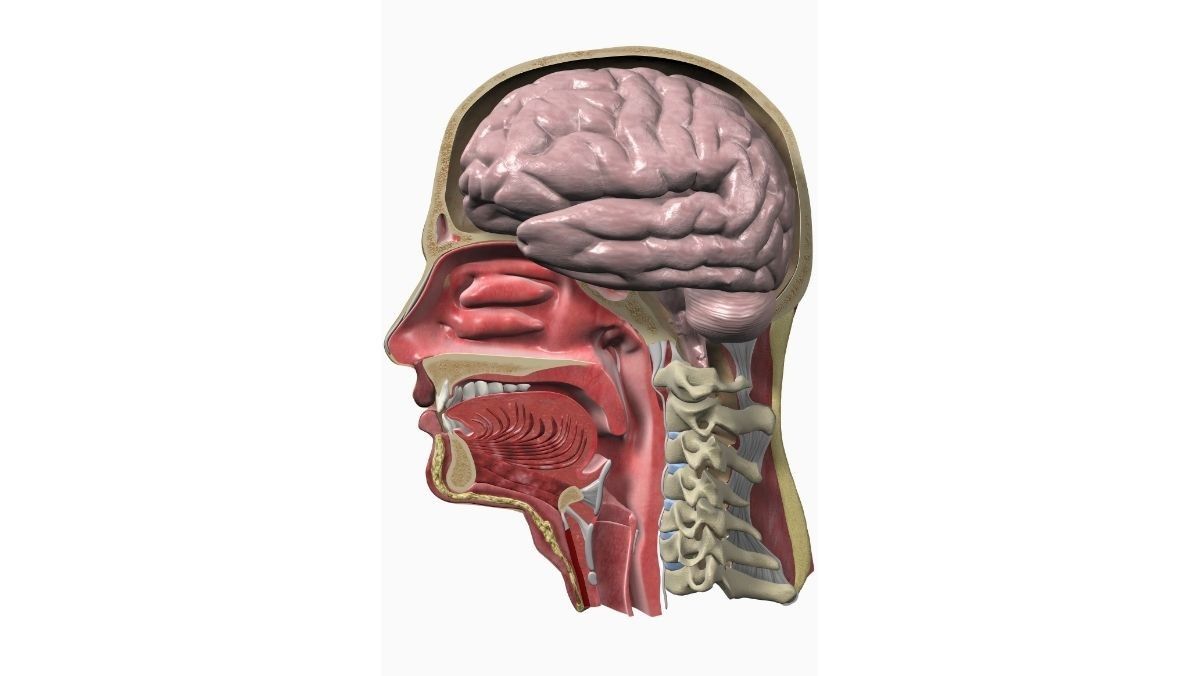

Fungsi Faring bagi Tubuh

Faring memiliki fungsi bagi sistem pernapasan dan sistem pencernaan. Pada sistem pernapasan, faring berperan membawa udara dari rongga hidung masuk ke trakea.

Sementara itu, dalam sistem pencernaan, faring berfungsi mengantarkan makanan dan minuman dari rongga mulut menuju kerongkongan.

Faring juga membantu manusia berbicara karena otot-otot organ tersebut dapat bergetar dan menghasilkan suara. Berikut penjelasan mengenai fungsi faring:

1. Menjadi Jalur untuk Masuknya Udara

Udara dapat masuk dari hidung hingga ke paru-paru melalui laring serta trakea. Terdapat isthmus di dalam faring yang membuat manusia bisa bernapas melalui hidung dan mulut.

2. Memisahkan Jalur Udara, Makanan, dan Air

Di bagian ujung faring terdapat epiglotis yang berfungsi mencegah udara memasuki sistem pencernaan. Selain itu, epiglotis juga mencegah makanan dan minuman memasuki saluran udara.

3. Membantu Menelan dan Mendorong Makanan ke Kerongkongan

Faring memiliki otot yang membantu menelan makanan. Otot faring dapat mendorong makanan dan minuman untuk turun ke usus.

5. Membantu Pelafalan Bicara

Faring merupakan organ dengan bentuk seperti ruang tertutup dan dapat berubah-ubah bentuk karena struktur ototnya. Oleh karena itu, udara dapat melalui faring saat menuju ke bagian laring (kotak suara).

Saat pita suara bekerja membuat suara, faring memiliki peran untuk memperkuat suara. Faring berfungsi memberikan suara pada kata pertama serta mendorong suara untuk keluar dari mulut.